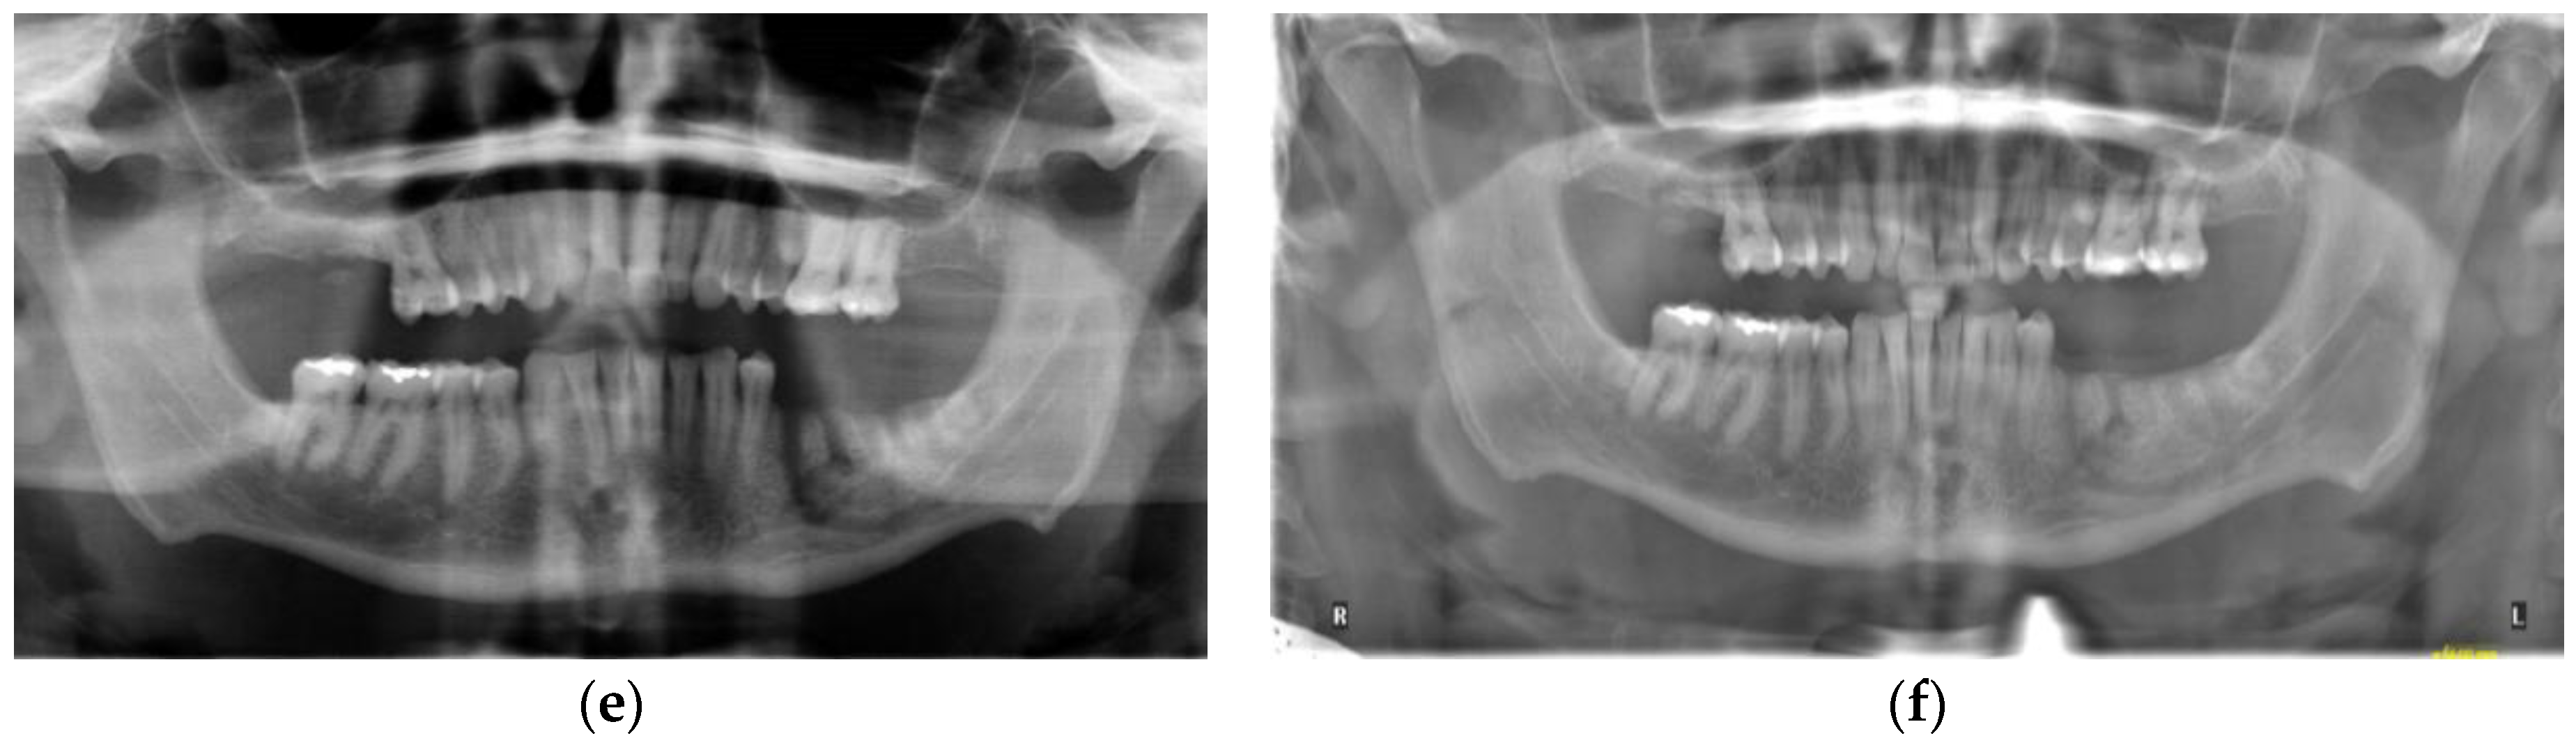

3.1. Case 1

3.2. Case 2

3.3. Case 3

3.4. Case 4

3.5. Case 5